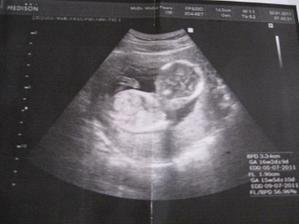

23.2. 2011 Byli jsme na velkém UTZ, ukázala se nám krásná zdravá holčička a pěkně čiperná 🙂